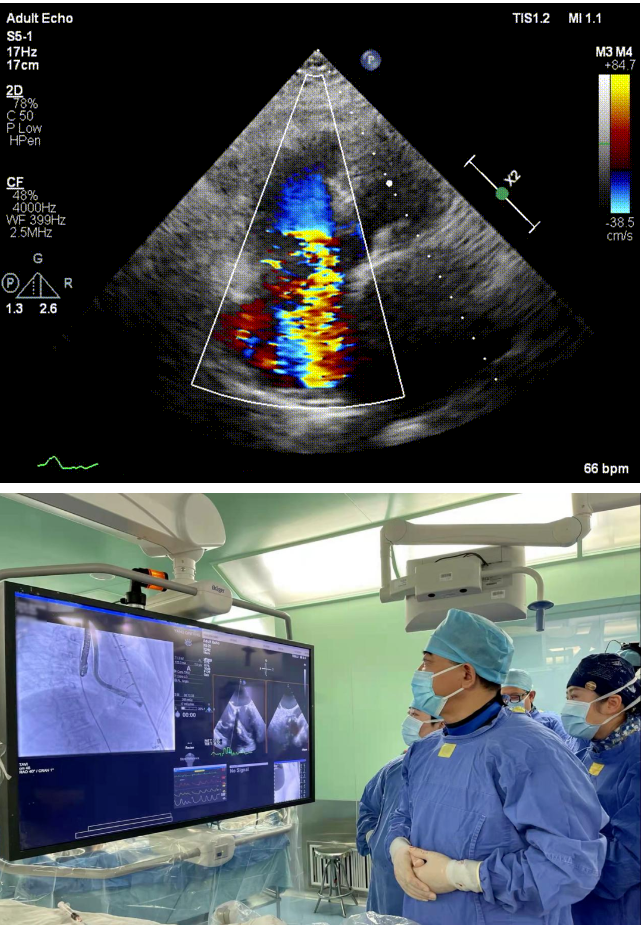

11月30日上午,復(fù)旦大學(xué)附屬中山醫(yī)院葛均波院士帶領(lǐng)的結(jié)構(gòu)性心臟病團(tuán)隊(duì)成功應(yīng)用Lux-Valve Plus經(jīng)血管三尖瓣置換系統(tǒng),為一位外科高危的極重度三尖瓣反流患者完成了經(jīng)頸靜脈入路三尖瓣置換術(shù),并獲得圓滿成功!葛均波院士、周達(dá)新教授、魏來(lái)教授、潘文志教授等和心超室的潘翠珍教授、李偉教授及麻醉科的郭克芳教授共同完成了本次手術(shù)。

本次接受治療的患者是一名74歲的女性,14年前因風(fēng)濕性心臟病行二尖瓣生物瓣植入術(shù),合并房顫。近3年來(lái)反復(fù)因腹脹、納差、下肢水腫入院,藥物治療欠佳。心臟超聲顯示三尖瓣極重度反流(有效反流口面積:0.76cm²,反流容積:79ml),繼發(fā)性右房室增大及上、下腔靜脈增寬(右房上下徑*左右徑:52*41mm,右室左右徑:46mm,下腔靜脈:29mm),右室收縮功能正常,肺動(dòng)脈收縮壓 43mmHg,左心室射血分?jǐn)?shù)73% ?;颊呒韧_(kāi)胸手術(shù)史,術(shù)前評(píng)估STS 評(píng)分為7.02分,CRS 9分,無(wú)法接受體外循環(huán)下三尖瓣外科手術(shù)。面對(duì)這一傳統(tǒng)治療無(wú)法解決的困境,葛均波院士及其團(tuán)隊(duì)周達(dá)新教授、潘文志教授、張?jiān)床┦?、陳莎莎博士及心超室的潘翠珍教授、李偉教授?jīng)過(guò)討論決定,采用創(chuàng)新的Lux-Valve Plus系統(tǒng)為患者進(jìn)行經(jīng)血管三尖瓣置換。

手術(shù)在患者全麻狀態(tài)下進(jìn)行,采用經(jīng)右側(cè)頸靜脈作為入路,將裝載有人工瓣膜的輸送器緩慢推送至右心房;并在經(jīng)食道超聲和DSA的引導(dǎo)下小心調(diào)整輸送器角度,將輸送器送入右心室;逐步釋放瓣膜錨定裝置和盤(pán)片,調(diào)整瓣膜位置后,錨定瓣膜完成植入。術(shù)后右房壓明顯下降,從術(shù)前的25/10(16) mmHg降至術(shù)后即刻的12/7(10) mmHg,術(shù)后超聲提示人工三尖瓣同軸性良好,固定牢固,無(wú)反流及瓣周漏,手術(shù)室即刻拔除氣管插管。